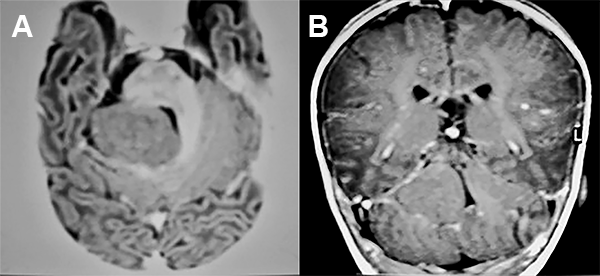

La RMN de encéfalo evidenció una lesión expansiva cerebelosa en contacto con el IV ventrículo y los pedúnculos cerebelosos superior y medio izquierdo, con leve efecto de masa que no realza con contraste (fig. 1).

Figura 1: Caso 1 imágenes prequirúrgicas.

A los 3 años de vida se realizó un abordaje suboccipital telovelar con una exéresis macroscópicamente total de la lesión con buena evolución post operatoria (fig. 2).

Figura 2: Caso 1 Imágenes postquirúrgicas.